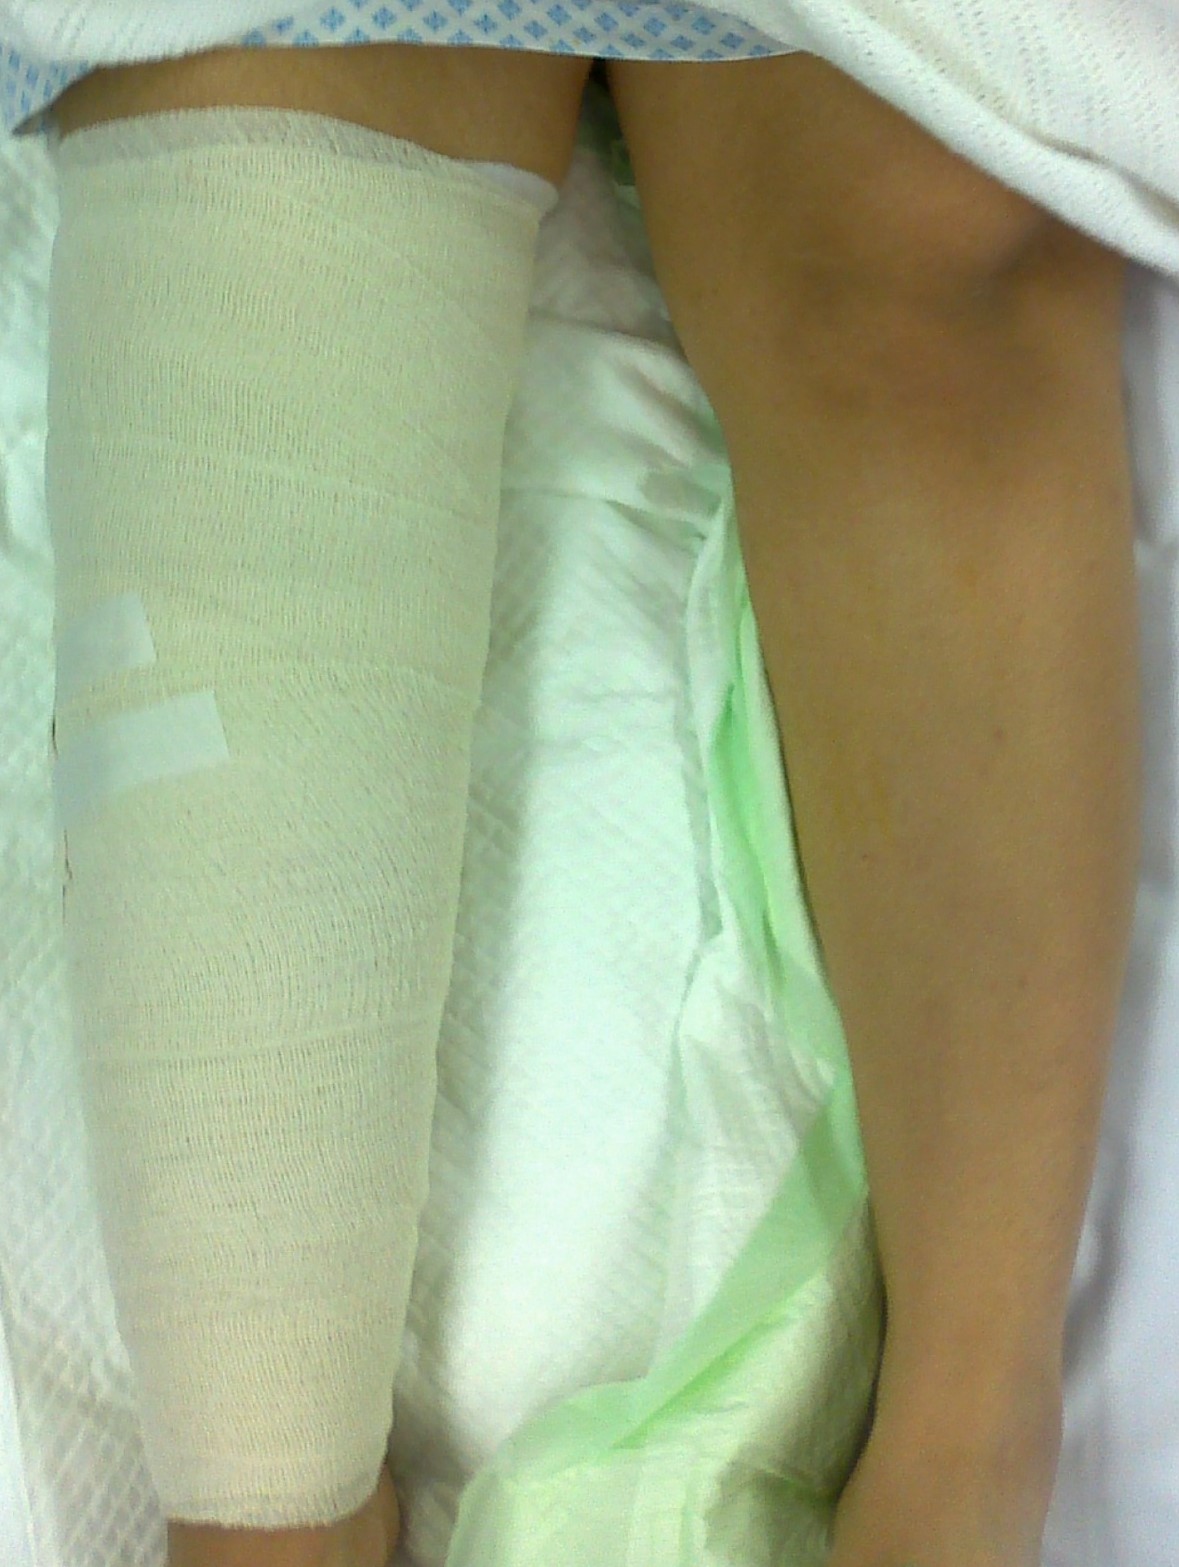

The surgeon in preparation for each surgery preconstructs a customized apparatus. Using wires or pins, the apparatus is surgically attached to the affected limb. Surgery is usually performed percutaneously through small incisions. Special care is taken to minimize injury to the bone and surrounding soft tissue, nerves and blood vessels when making specialized bone cuts.

Generally, patients remain in the hospital for 3 to 7 days before they are discharged home. A more complex procedure may require a longer inpatient stay.

The actual lengthening or straightening of the limb begins 1-2 weeks after surgery. At that time, adjustments are made to the apparatus usually four times a day. Detailed instructions are provided to the patient to ensure they fully understand what is required.

Swimming and showering are allowed with the apparatus in place once initial wound healing has occurred at 5-7 days postoperatively.